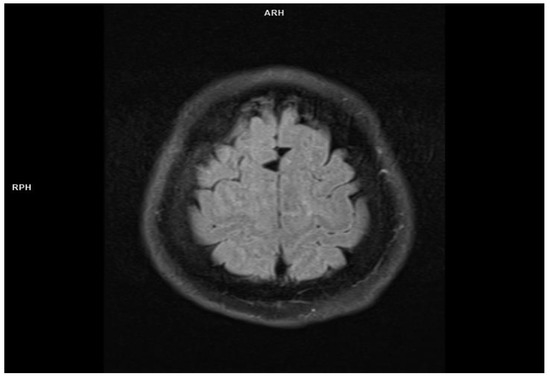

2.1. Patient 1